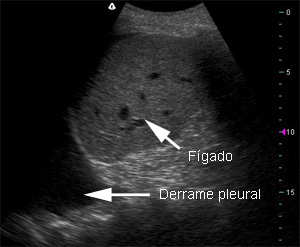

A ascite severa, com grande aumento do abdome, é facilmente identificável. Há um aumento no desconforto, na sensação de “peso” e há também dispneia (falta de ar). A dispneia pode estar diretamente relacionada à quantidade de líquido e piora quando o paciente está deitado, pois a ascite pressiona mais ainda o diafragma, reduzindo o volume dos pulmões. Mesmo assim, a dispneia pela ascite deve ser diferenciada da causada por insuficiência cardíaca, da síndrome hepatopulmonar e do hidrotórax.

Para fins de classificação da cirrose na escala de Child-Pugh, a ascite é dividida entre “ausente”, “leve” e “moderada/severa”. A ascite leve englobaria a ascite observada apenas por exame de imagem (como a ultrassonografia) e a observada no exame físico, mas sem grande aumento do volume abdominal. A ascite moderada seria a que leva a aumento significativo no abdome, mas sem a presença de falta de ar (dispneia) e/ou de abdome tenso pela grande distensão, que seriam característicos da ascite severa.